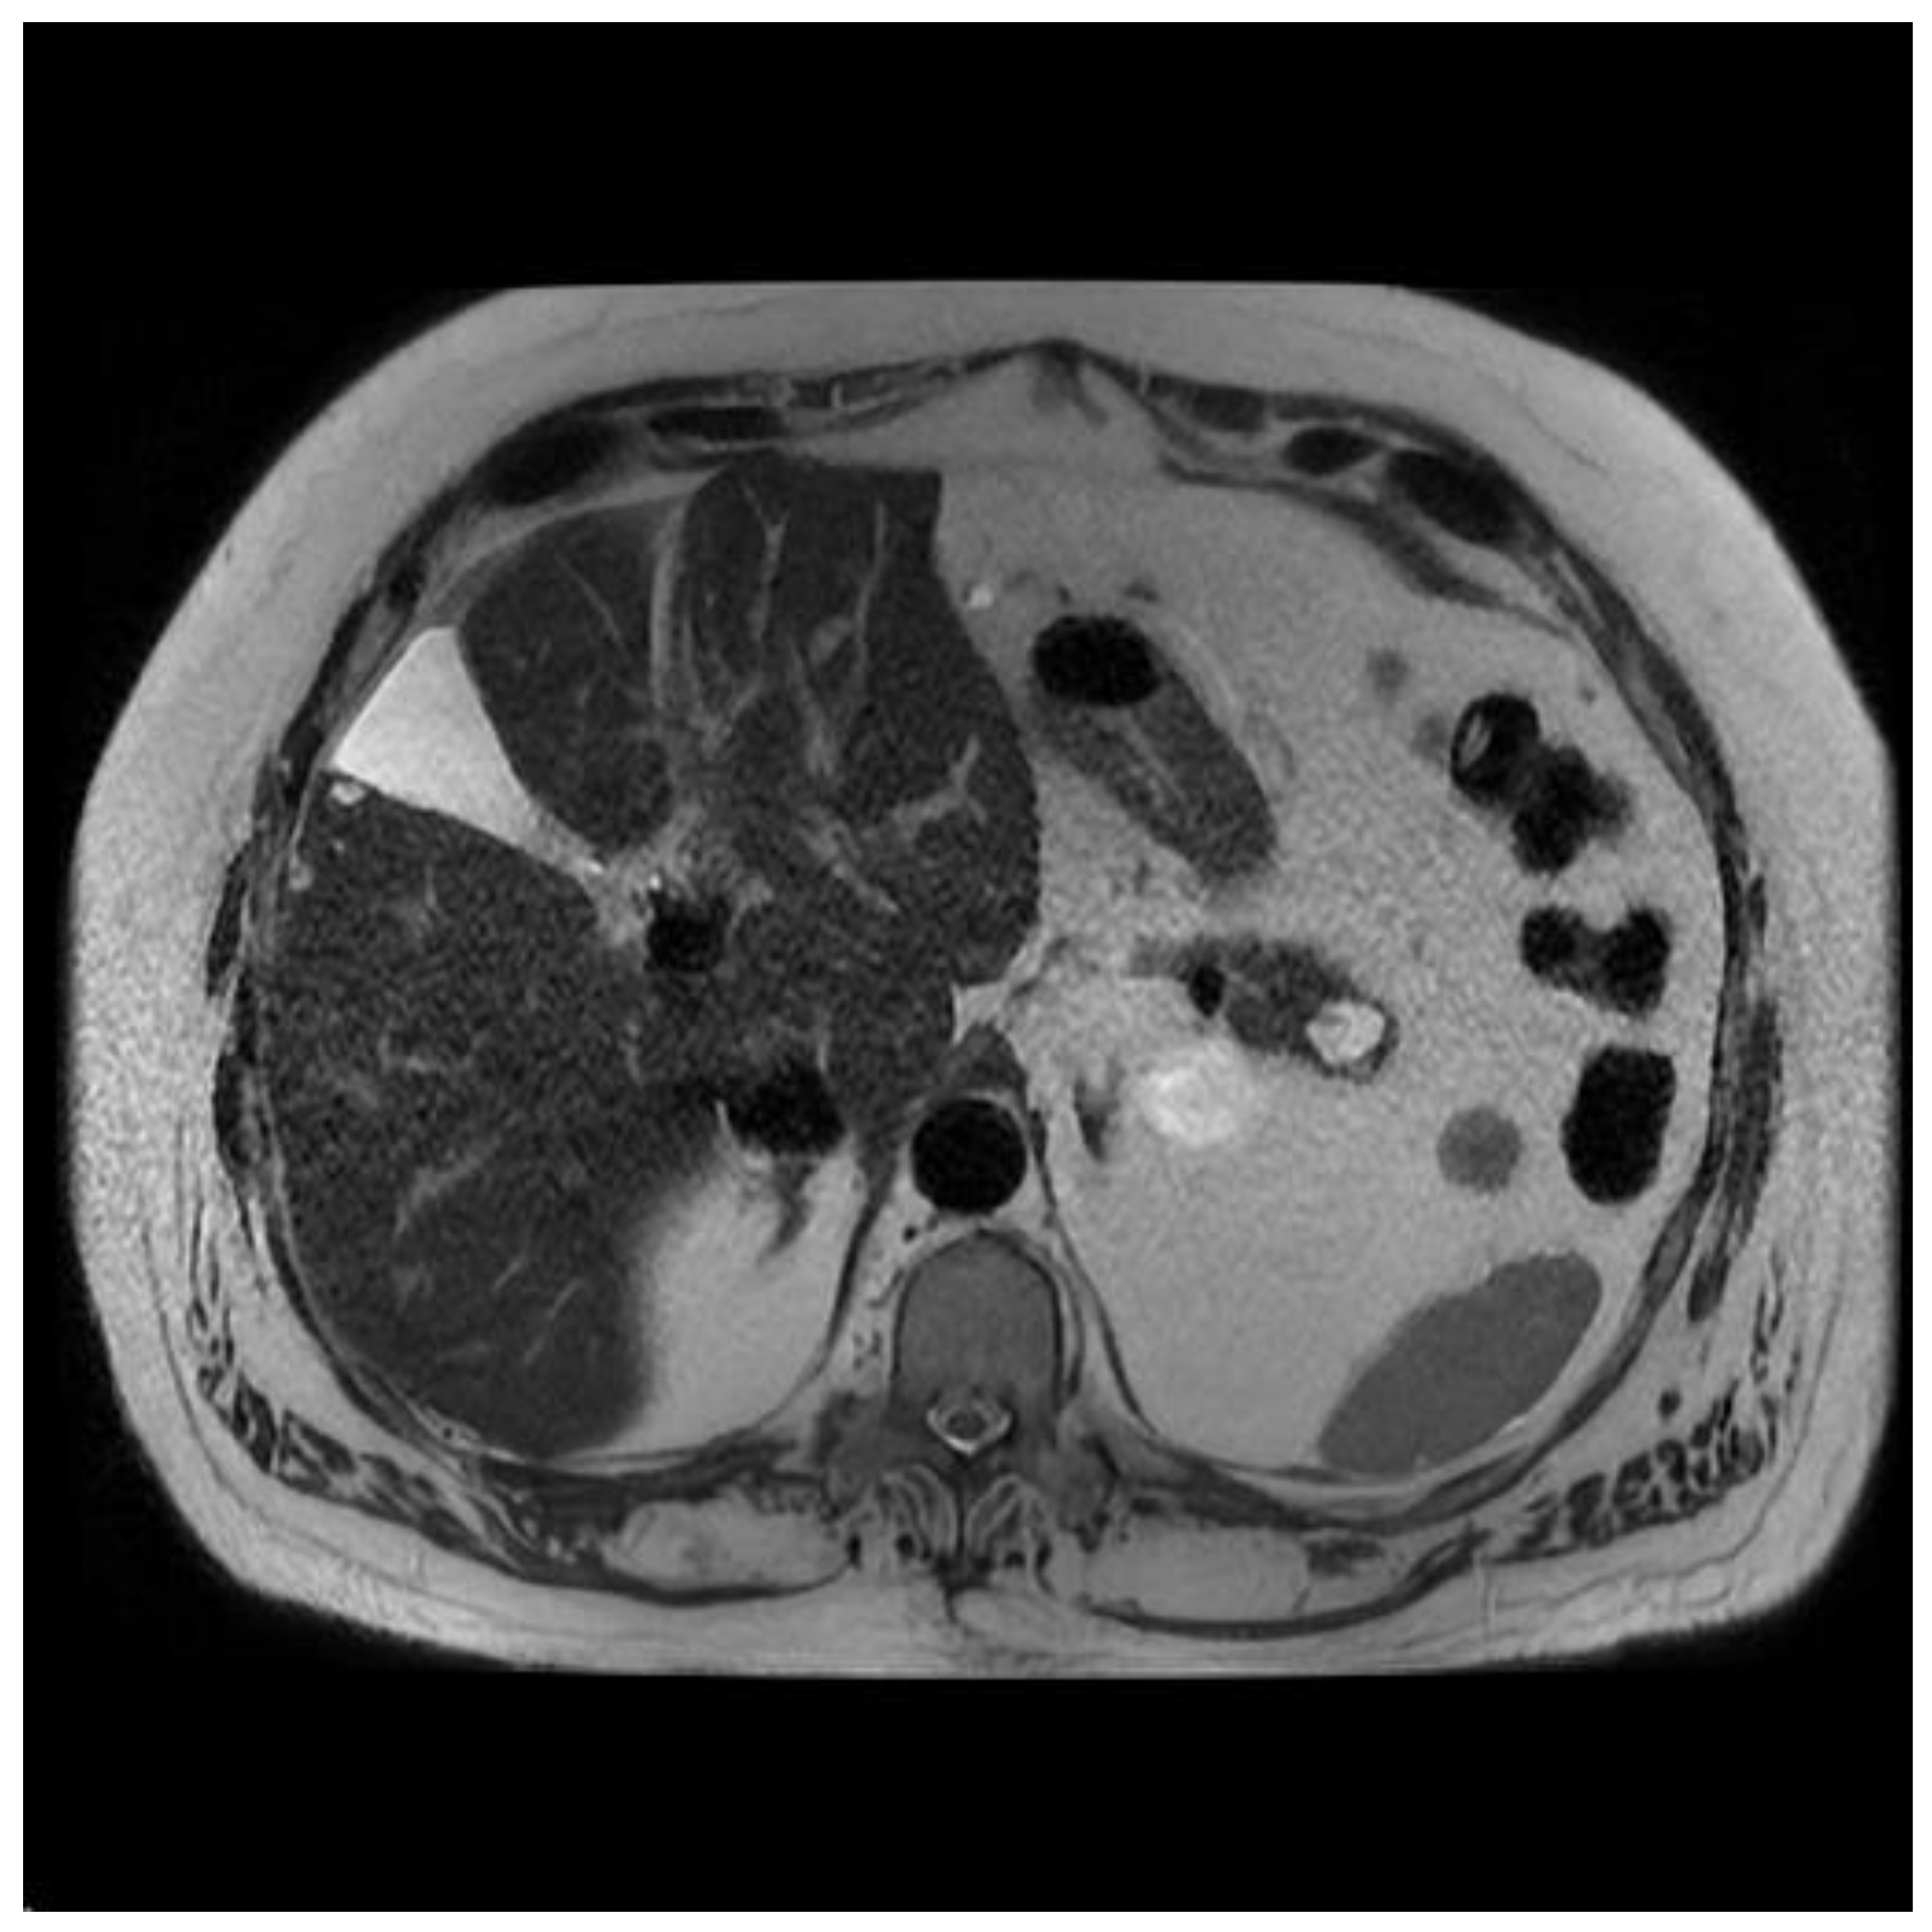

Figure 2.

(a) EUS image of main duct IPMN; (b) MRI image of main duct IPMN.